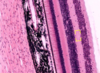

Endocrine pancreas cells

Pancreatic acini (with exocrine cells) - dark purple

Pancreatic islet (with endocfine cells) - light purple

Islet of Langerhans (endocrine pancreas), surrounded by serous acini (exocrine pancreas)

Assume that most cells in middle of islet are beta and cells at periphery of islet is alpha cells